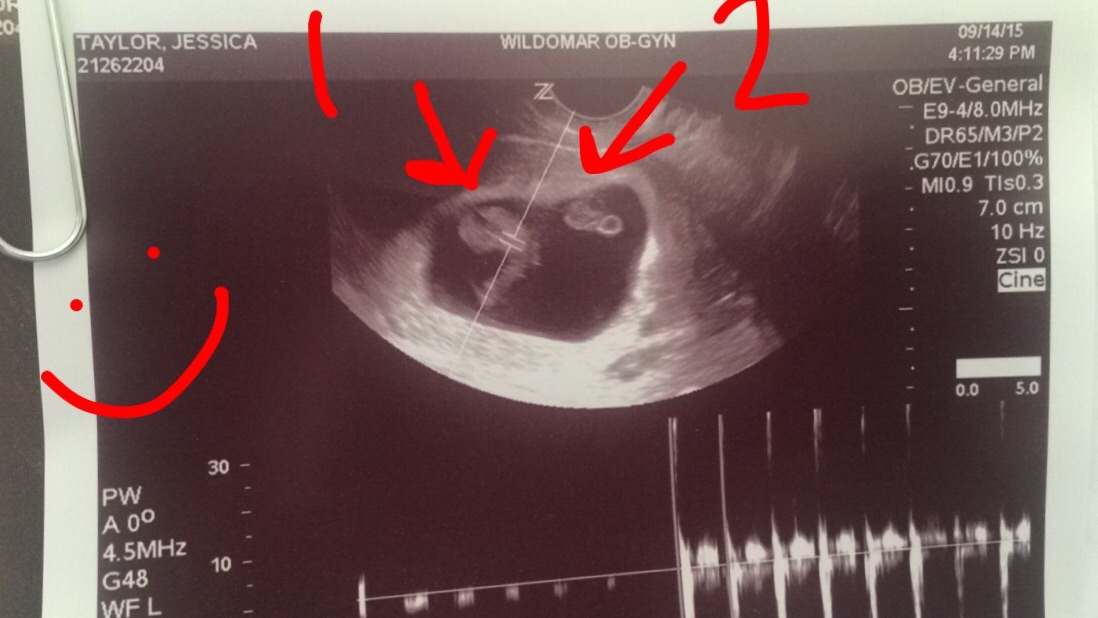

• After a MC in March, I needed this second US to make me feel better about this pregnancy! Loving this little lime - measuring 11w5d